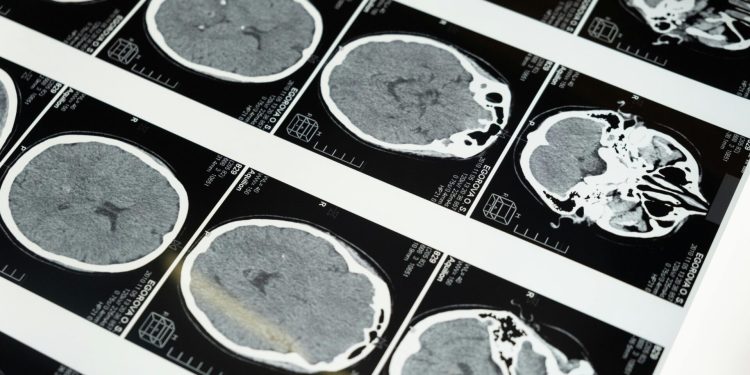

Geliştirilen derin öğrenme framework’ü, SLIViT (SLice Integration by Vision Transformer), retinal taramalar, ultrason videoları, CT, MRI gibi farklı görüntüleme modlarından gelen verileri analiz ederek potansiyel hastalık riski belirteçlerini tespit ediyor.

Mevcut durumda, tıbbi görüntüleme uzmanları genellikle aşırı yükleniyor ve hastalar, X-ray, MRI veya CT taramalarının değerlendirilmesi için haftalarca beklemek zorunda kalıyor.